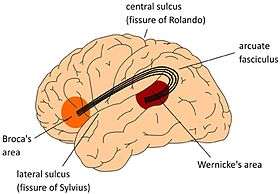

Arcuate fasciculus connects Broca's area and Wernicke's area.